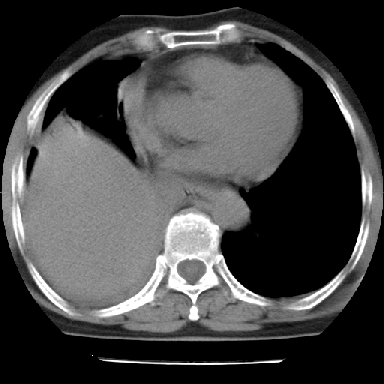

以下是引用苯小孩在2007-4-13 16:20:00的发言:[br]1、右下肺中央型肺癌并阻塞性肺不张、肺内转移、胸椎右侧附件亦有转移<横断层面第8层>.[br]2、右侧胸腔积液.

以下是引用swyyy2007在2007-4-13 15:31:00的发言:[br]右肺门下区肿块,右肺下叶支气管阻塞,右肺下叶不张,右侧大量胸腔积液,右肺中叶见结节状高密度影,边缘清,纵隔内见肿大淋巴结。首先考虑右下肺中心型肺癌伴右肺下叶不张、中叶、纵隔淋巴结转移。右侧胸腔积液。